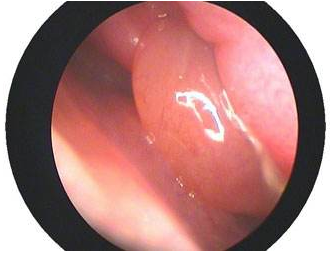

(鼻部結(jié)構(gòu)圖)

8、鼻腔粘膜出現(xiàn)淡紅或者暗紅,下鼻甲肥厚但是彈性較差。

(慢性鼻炎的危害鼻息肉)